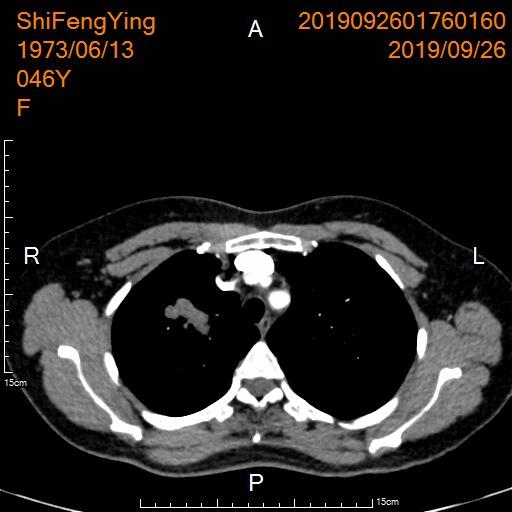

例4:右肺不典型类癌(G2)并多发脑转移

中年女性,头晕、头痛伴肢体乏力1月余。肿瘤标志物不同程度升高。

肺部CT显示右上肺恶性肿瘤并右肺门、纵膈淋巴结转移

肺窗

动脉期

静脉期

CT引导下右肺肿物穿刺活检病理:不典型类癌(Ki-67 约55%)。